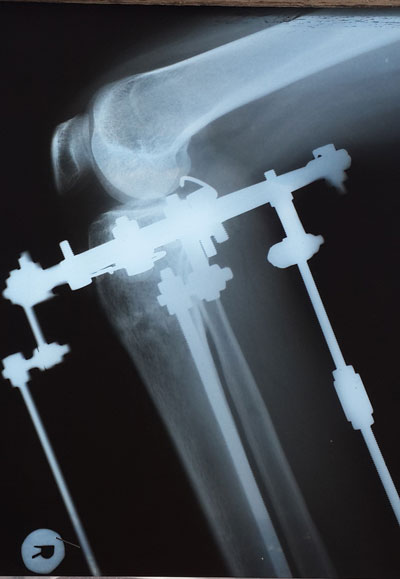

Рентген контроль в 1,5 месяца с момента снятия аппаратов.

Всё в норме! Разрешено все нагрузки без ограничения, каблуки любых размеров! Фото на каблуках за Вами!